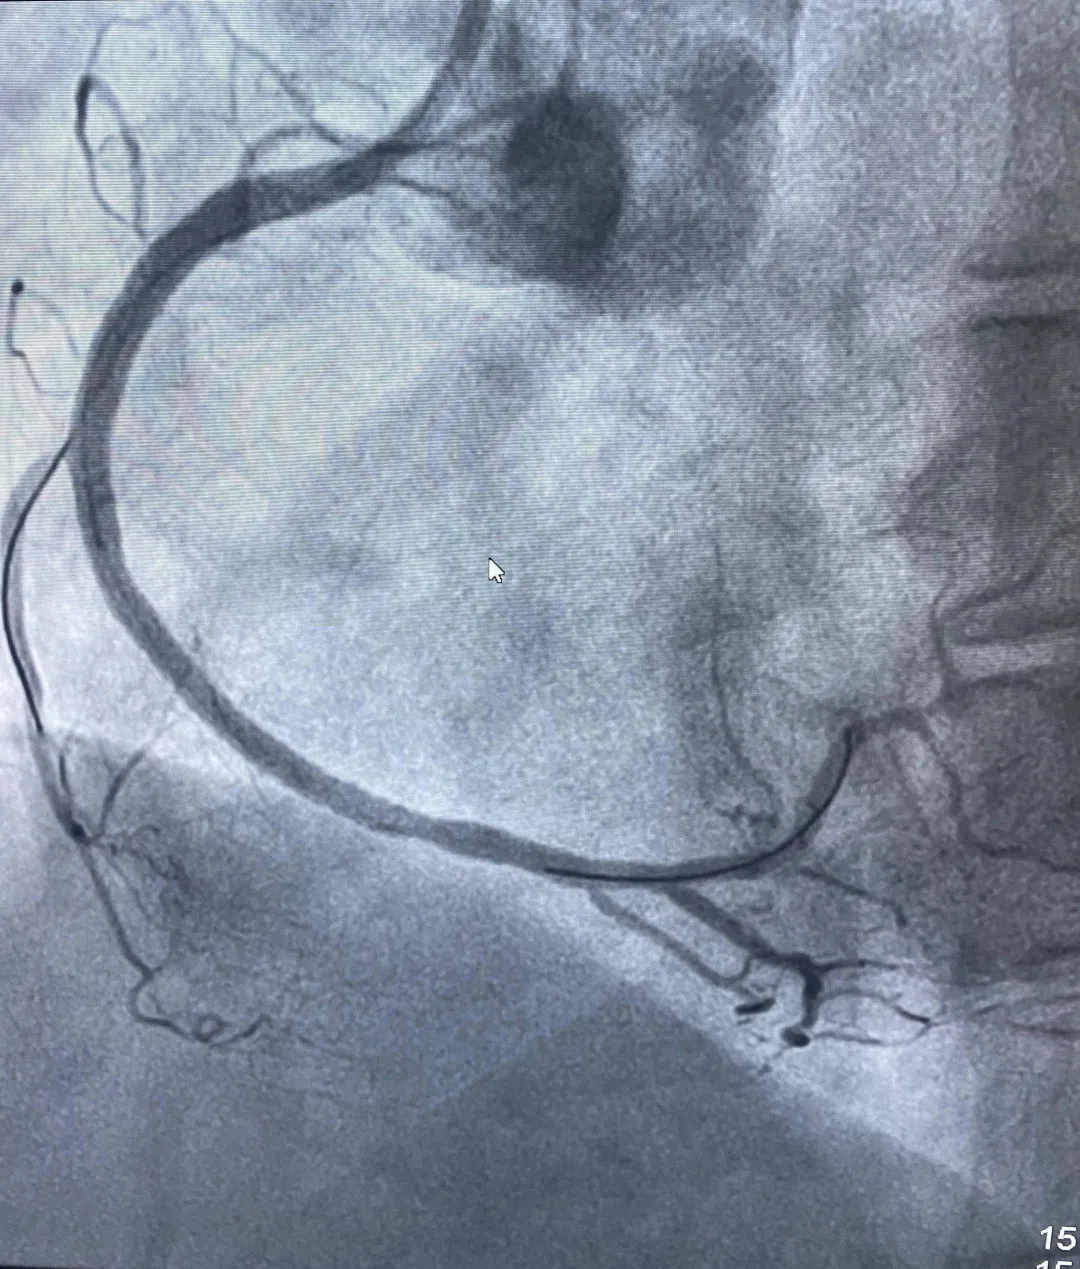

术后右冠完全开通